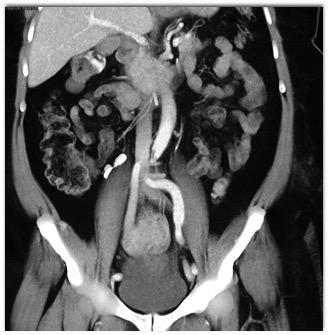

On this study done with IV contrast in the patient with a drop in hematocrit the best diagnosis is?

active bleed in hepatic flexure